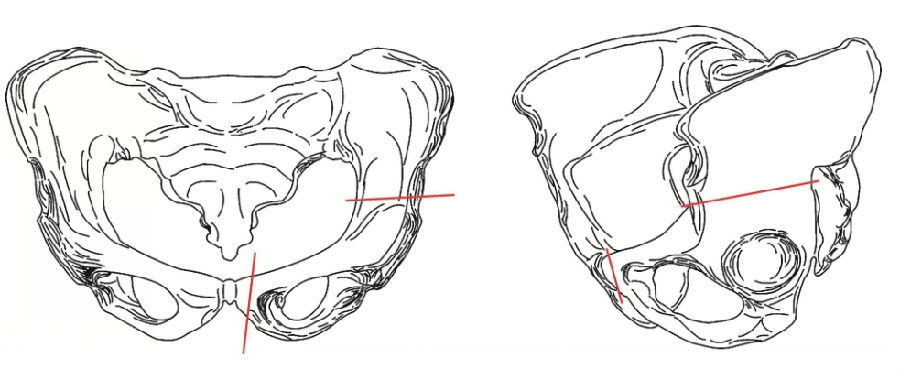

1977年,Sutherland报道骨盆双联截骨术,用于解决前述局限,治疗较大年龄患者的DDH。本手术是在完成Salter骨盆单一截骨后,再在耻骨联合和耻骨结节之间截骨,因此称为Sutherland骨盆双联截骨(图1)。由于增加了耻骨联合处的截骨,它可获得比骨盆单一截骨术更多的自由度,髋臼能充分旋转,改善其对股骨头的覆盖。采用Steel三处髂骨截骨术虽然也能增加髋臼的旋转度,但本术式手术损伤小,方法较简便。

图1 Sutherland截骨位置示意图髂骨截骨的位置与Salter单一骨盆截骨相同,注意耻骨联合处截骨需确保:截骨内侧段保留少量松质骨和外侧段保持闭孔的完整性。